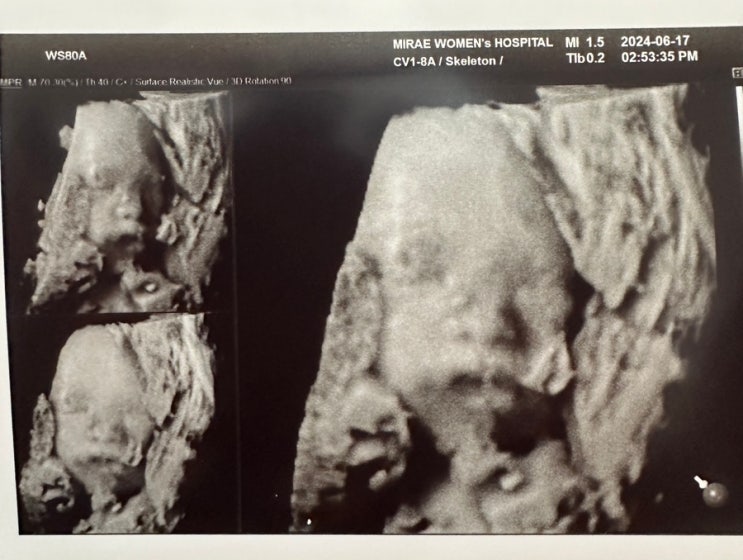

32주 4일 차 30대 중반이 되어서 진정한 행복을 느끼며 살아가고 있다. 물론 그전에도 행복하지 않았다는 ...